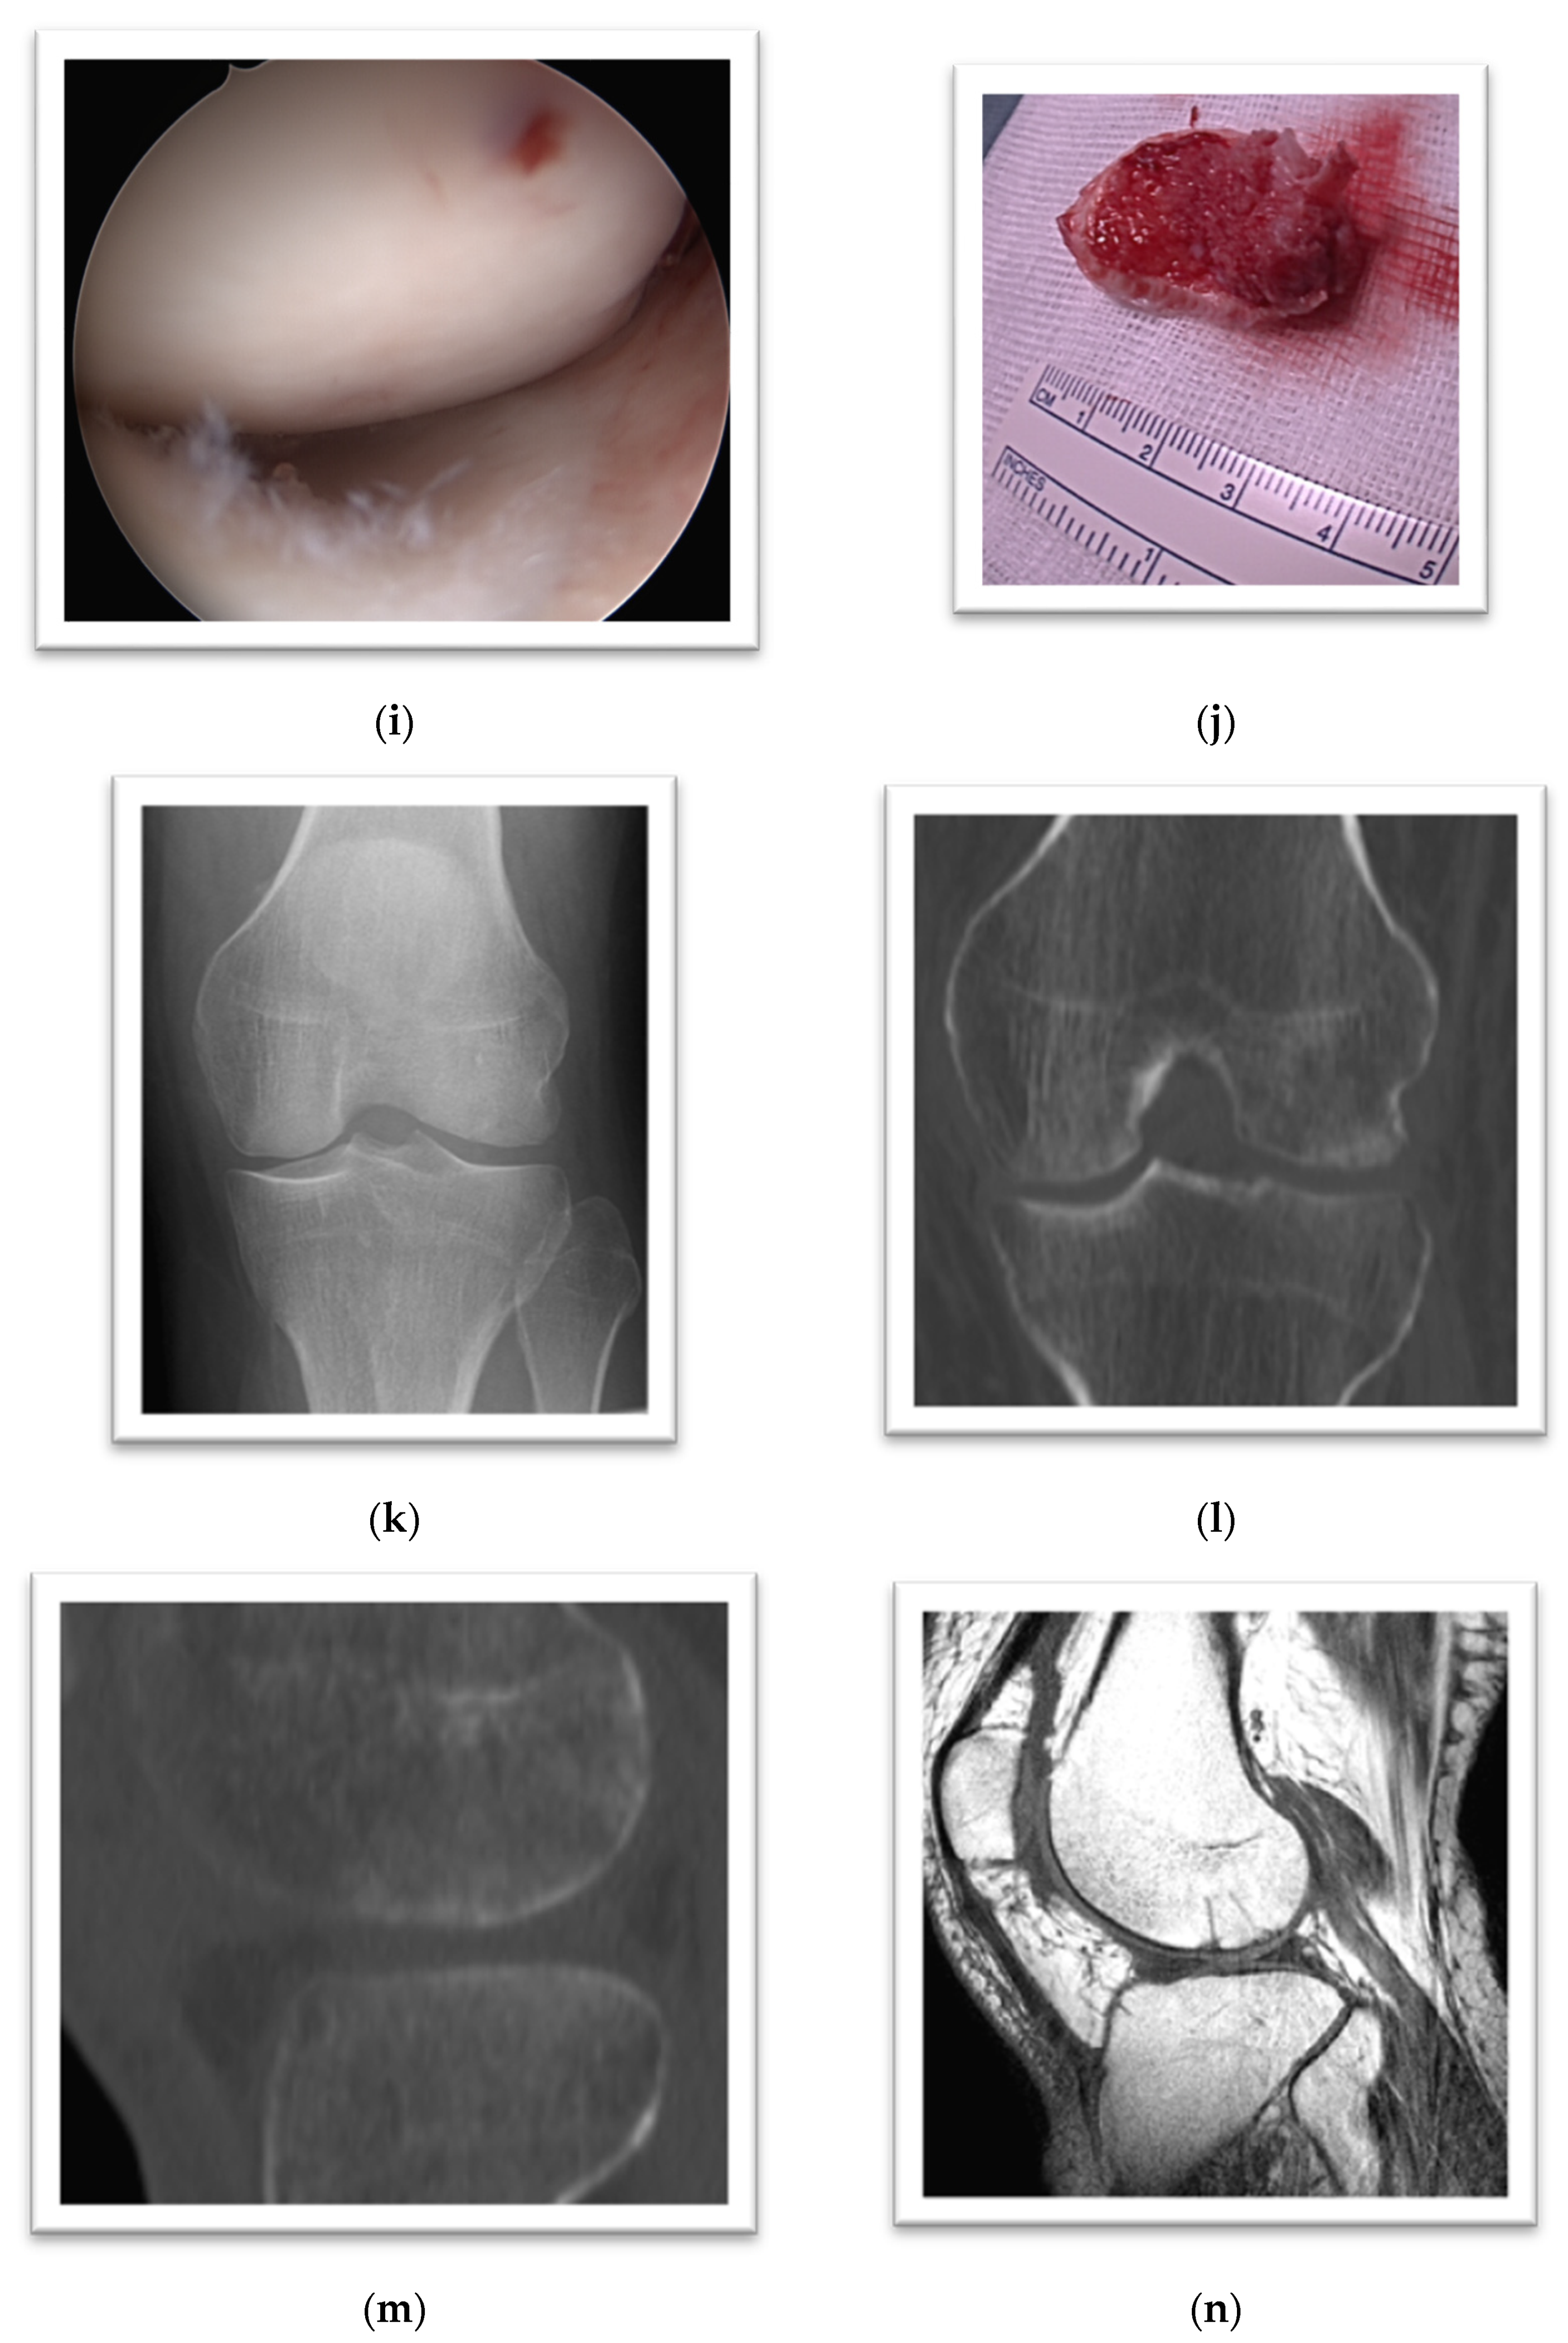

3. Case Presentation

4. Case Presentation

5. Case Presentation